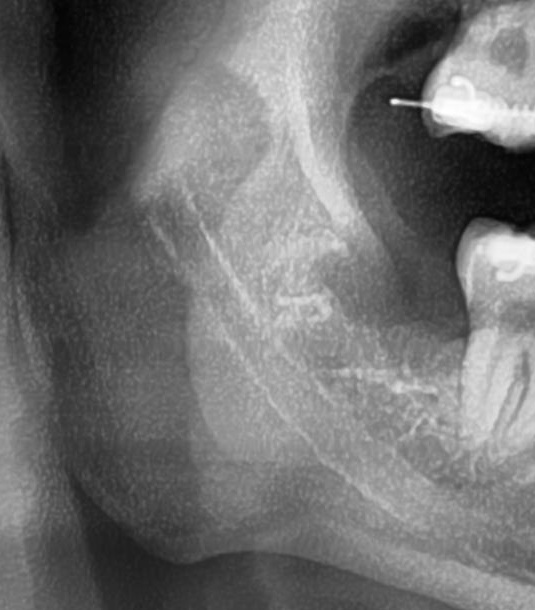

次にパノラマ写真を撮影してみると、右下の親知らずは手前の歯を押すように斜めに生えているのが確認できました。